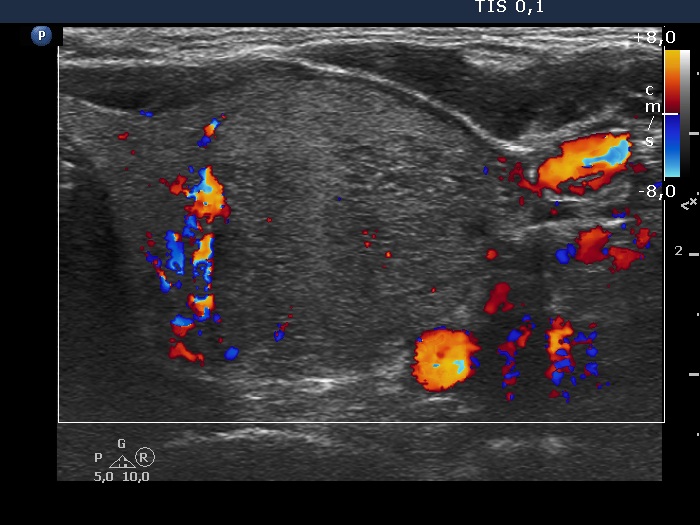

Right lobe, longitudinal scan

Left lobe, transverse scan, color Doppler mode.